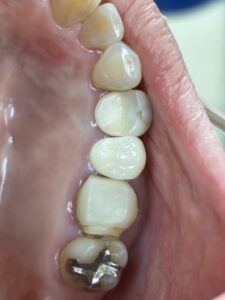

金属アレルギーの原因になる得る、銀歯を白くしたいという患者さんがいますが、保険適応でCADCAMやハイブリッドセラミックで治療してくれる歯科医院が、相変わらず少ないと言う患者様が来院されますね。

セラミックインレーやジルコニアクラウンもおすすめです。これらは自費ですが。

違いや比較としては 保険のは年数が経過すると 劣化したり変色する 欠けたり割れたりする可能性があります。

保険適応でCADCAMやハイブリッドセラミックインレー クラウンをしたいなという方はご予約ください。